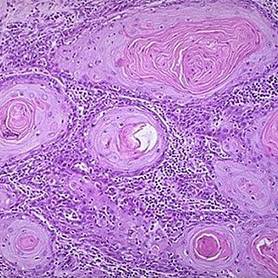

首先我们需要了解的是,宫颈癌的发生是一个漫长的过程,包括由人类乳头状瘤病毒(HPV)感染引起的细胞相关改变到癌前病变ⅠⅡⅢ级(CINⅠⅡⅢ级)再到侵袭性癌。

LSIL(低级别鳞状上皮病变)、HSIL(高级别鳞状上皮病变)、ASC-H(不能除外高级别上皮内病变)。这三个诊断结果均提示需要进一步做阴道镜检查+宫颈活检,说明医生在显微镜下观察到细胞已经出现异型改变,只是程度不一。虽然活检结果不一定异常,但提示出现宫颈癌癌前病变(CIN病变)或侵袭性病变(癌)的机率比较大。